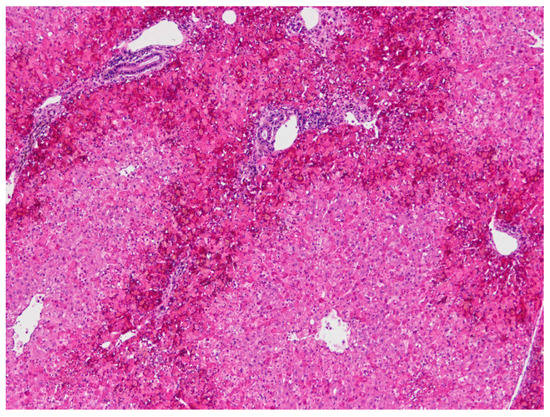

The following microscopic lesions were observed: Liver: severe generalized perilobular haemorrhagic necrosis (Figure 3 and Figure 4). Discrete infiltration by mononucleated inflammatory cells, mainly macrophages and lymphocytes, around portal triads. Fine brown pigment in the cells of the portal bile ducts. Spleen: diffuse necrosis of the entire red pulp revealed by deposition of fibrinoid acidophilic material drawing serpiginous patterns in the parenchyma (Figure 5). The regular presence of lymphoid follicles around central arterioles. Pancreas: interlobular oedema and necrosis of adipocytes, both intralobular and interlobular. No changes were present in the secretory cells. Stomach: no significant changes were observed. Small intestine: Necrotic enteritis, particularly in the duodenum, with loss of villi and deposition of fibrin in the proximal mucosa (Figure 6). Kidneys: the areas of surface retraction in both kidneys corresponded to segmental fibrosis affecting cortex and medulla. In these areas, there was a loss of tubules and glomeruli, which were moderately congested. No microbial agents were identified in any organ and the results of the microbiological analysis were also negative.

Figure 3. Liver. Severe haemorrhagic necrosis consistently affects perilobular areas or acinar zone 1, conspicuous due to the bright red colour close to the portal areas (H&E, 40×).

Figure 5. Spleen. Severe diffuse fibrinoid necrosis of the red pulp. The eosinophilic material fibrinoid material is very abundant between the lymphoid tissue that surrounds blood vessels (H&E, 40×).